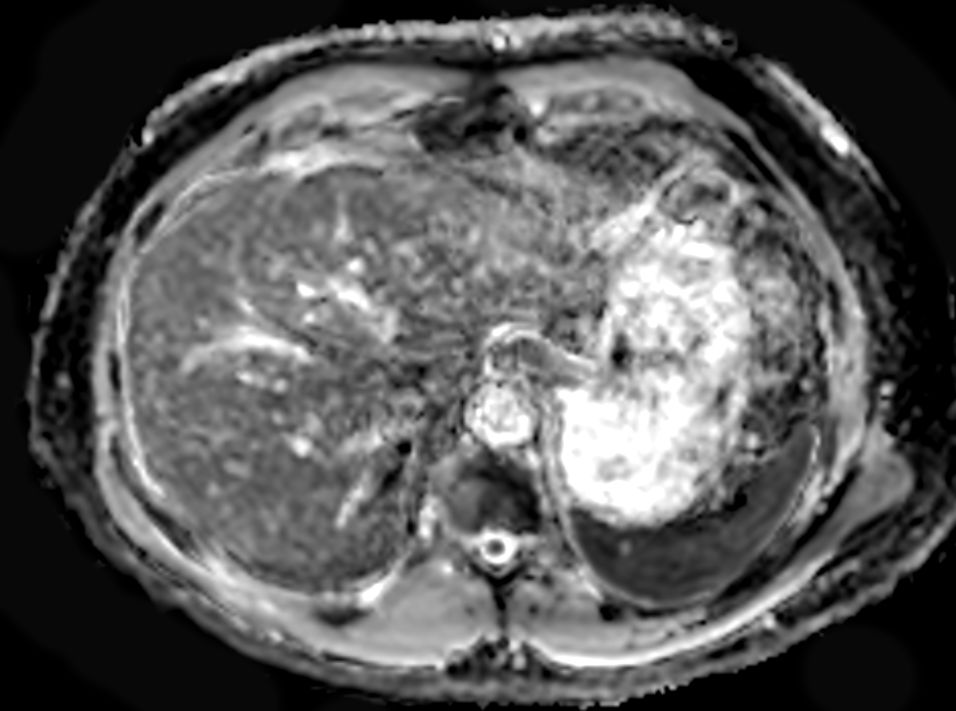

Axial T1w 3D VANE XD (water only)SmartSpeed 3D FreeBreathing